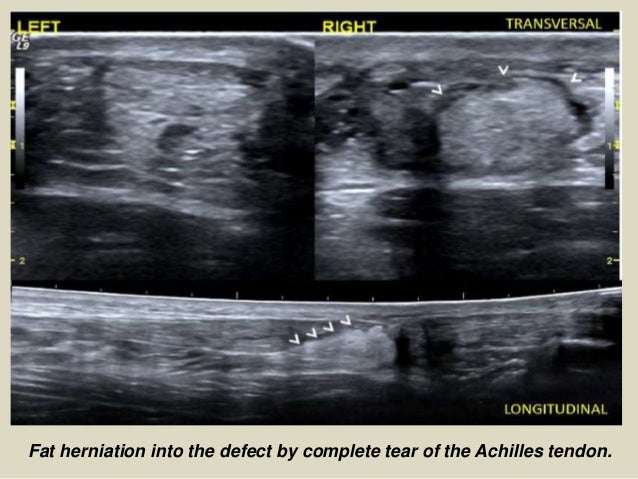

24. 24. Fat herniation into the defect by complete tear of the Achilles tendon.

19. 19. POSTERIOR COMPARTMENT ACHILLES TENDINOPATHY Can be classified as tendinosis and paratendinitis. The isolated paratendinitis shows intratendinous normal structure, exist paratendinitis spill, shown irregularities in the edges of the tendon, adhesions and scarring associated paratendon and a heterogeneous aspect preachilles fat pad. In the tendinosis there is in swelling of the tendon, usually bilateral, and textural heterogeneity intratendinous focal hypoechoic areas. TEAR OF ACHILLES The rupture site is located generally between the 2 and 6 cm from the insertion into the calcaneous, in the called critical zone of relative hypovascularity. In ultrasound, complete rupture of the Achilles tendon is seen as a focal defect between the broken ends of the tendon. In the acute phase ends are contiguous, but the defect may be filled by the anechoic or hypoechoic hematoma. In most cases paratendon remains intact as a envelope straight echogenic contouring breakage. As a sign associated can exist distortion of the fibrillar configuration and loss of parallelism of the tendon fibers. Other signs are indicative fat herniation into the defect, better visualization of the plantar tendon and the existence of a posterior acoustic shadowing at the site of the tear (useful sign to differentiate partial thickness tears).

Fat herniation into the defect by complete tear of the Achilles tendon.